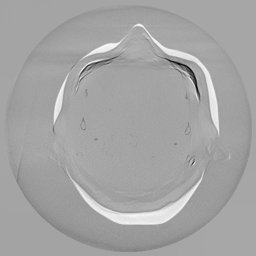

To assess the uncertainty of our method, we performed multiple reconstructions using different random seeds. As shown in Fig. 3, the ground truth and representative sampled images are presented in Fig. 3(a) and (b–d), respectively. The mean reconstruction and pixel-wise standard deviation across runs are displayed in Fig. 3(e) and (f). Only minimal differences are observed between reconstructions, indicating that I2SB produces highly consistent results. These findings confirm that, compared with classical diffusion models, I2SB substantially reduces uncertainty across repeated reconstructions.